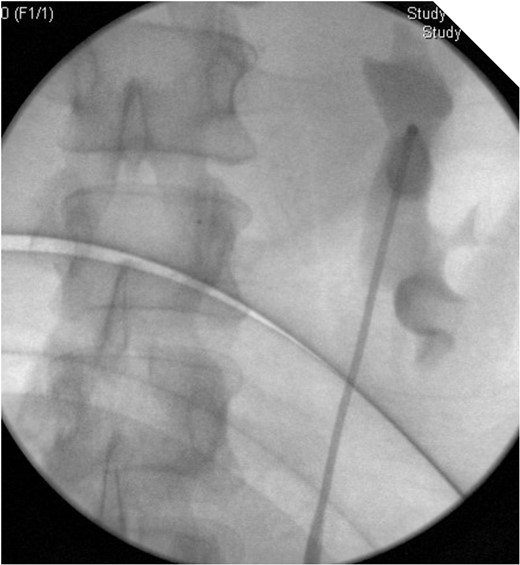

On Day 9 since presentation a CT IVU was repeated. This showed the stent in the left ureter to be in situ with no further leakage from the known rupture.

On table Pyelogram confirmed intact left collecting system and ureter.